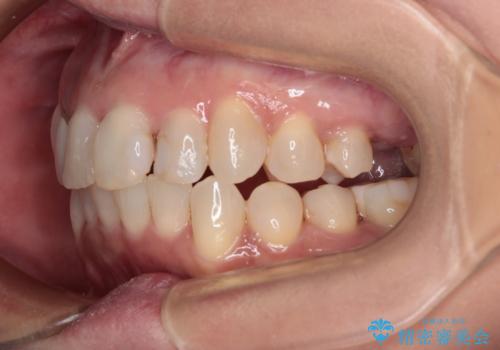

前歯のデコボコとむし歯治療の跡 インビザライン矯正とオールセラミッククラウン治療

- 前歯のセラミッククラウンの縁が見えることが気になってから、デコボコも気になるようになってきたとのことで来院された患者様です。

デコボコの程度は中等度であったため、インビザライン・モデレートパッケージにて歯列を整えることとしました。

セラミッククラウンの装着されていた前歯と、大きな修復治療の跡がある反対側の歯は、矯正治療後に補綴治療を行うこととしました。